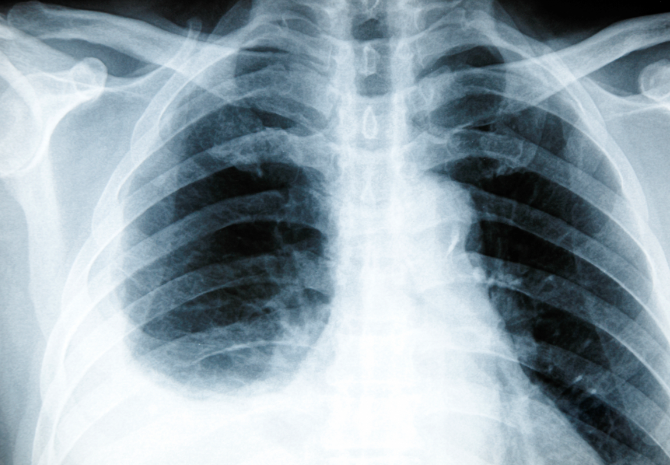

1) 영상 검사

- 흉부 X선 : 기본적인 검사로, 늑막강의 액체 축적이나 흉막의 두께 변화를 확인할 수 있습니다.

- CT 스캔 : 더 정밀한 이미지를 제공하여 늑막의 상태, 흉막삼출의 양, 그리고 다른 흉부 구조물의 이상을 파악하는 데 유용합니다.

- 초음파 : 늑막강의 액체 상태를 평가하고, 흉막삼출의 유무를 확인하는 데 사용됩니다.